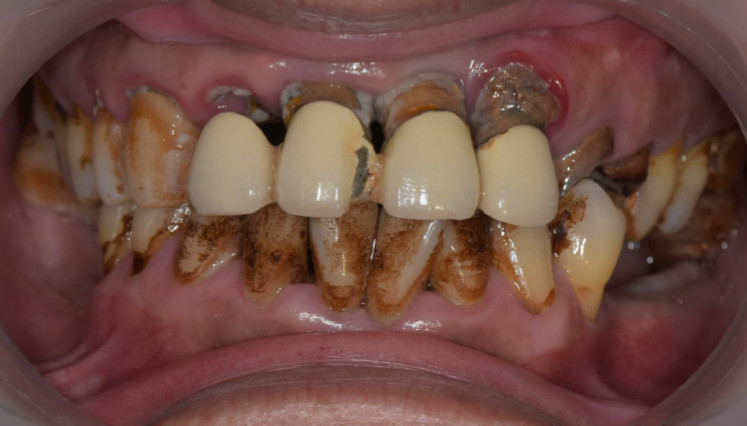

活動式假牙案例

牙齒狀況改善

治療前

治療後

這些照片展示了您的牙齒在術後得到顯著改善,排列更加整齊、美觀,並達到理想的咬合狀態。

也能增強口腔健康。